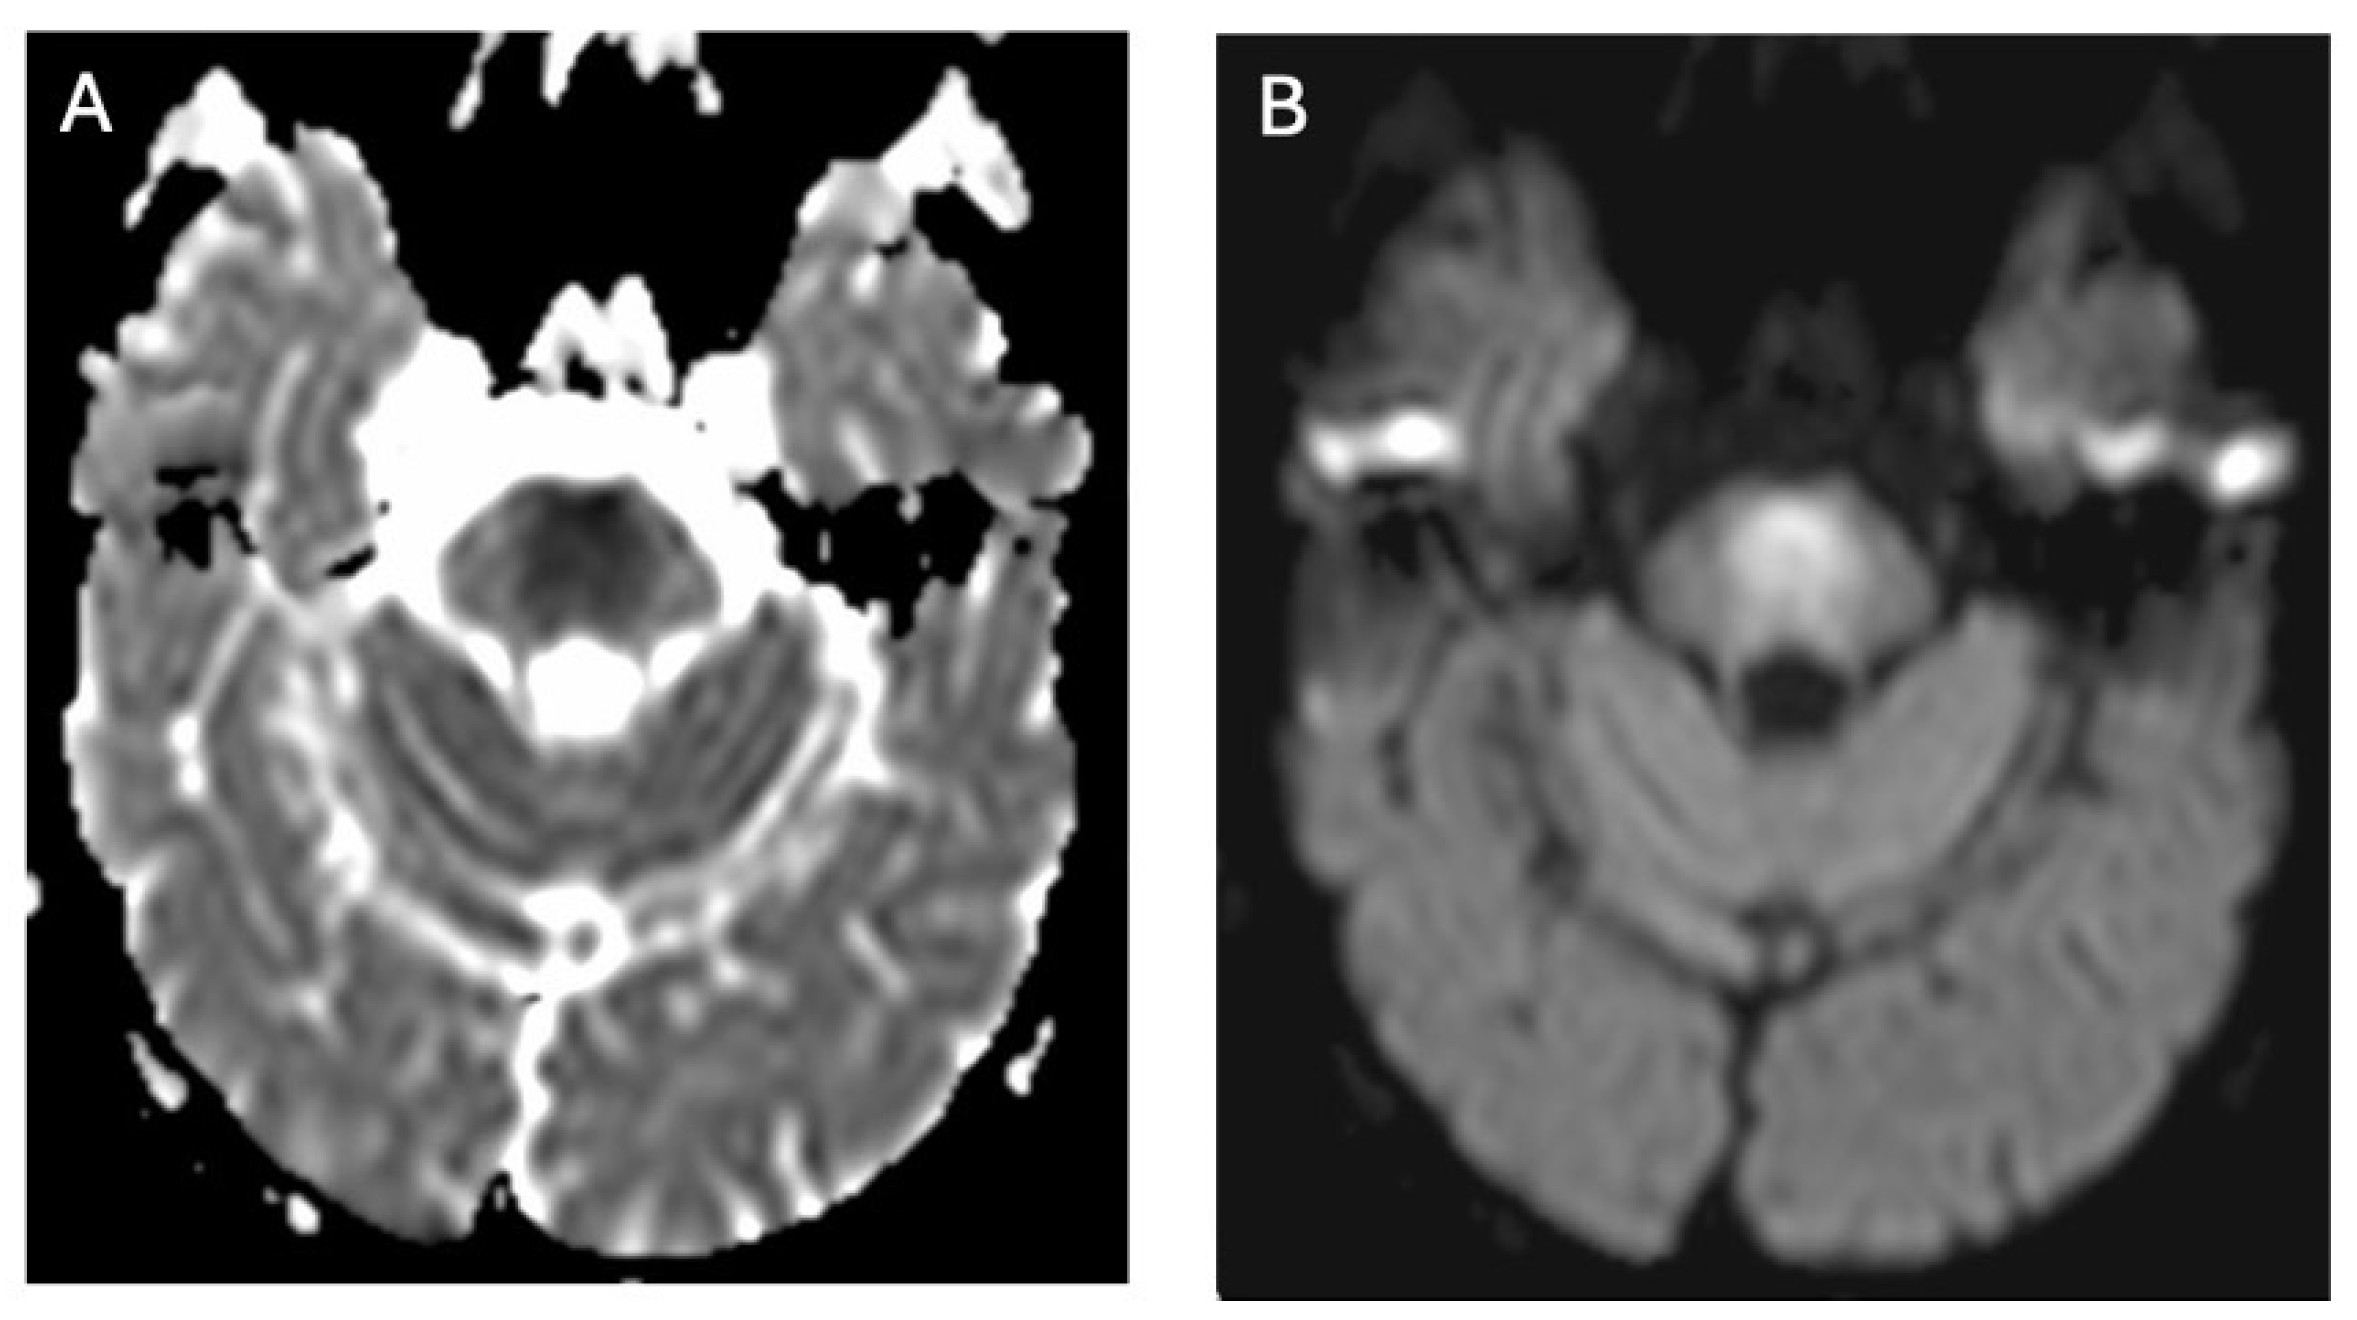

In WD, diffusion abnormalities can manifest as both restricted and increased diffusion (Figure 5). Diffusion restriction is relatively uncommon and typically appears in the early stages of the disease, presenting as hyperintense foci on T2-weighted and FLAIR images, indicative of edematous changes [32,33,34,35,36,37]. Increased diffusion, observed in structures such as the putamen, globus pallidus, internal capsules, midbrain, pons, and white matter, likely reflects neuronal loss, gliosis, and spongiosis [36].

Neuroimaging findings of WD affecting the pons—a hypointense signal on ADC maps (A) and a hyperintense signal on diffusion-weighted imaging (DWI) (B), indicative of cytotoxic edema (own materials of the neurology department).